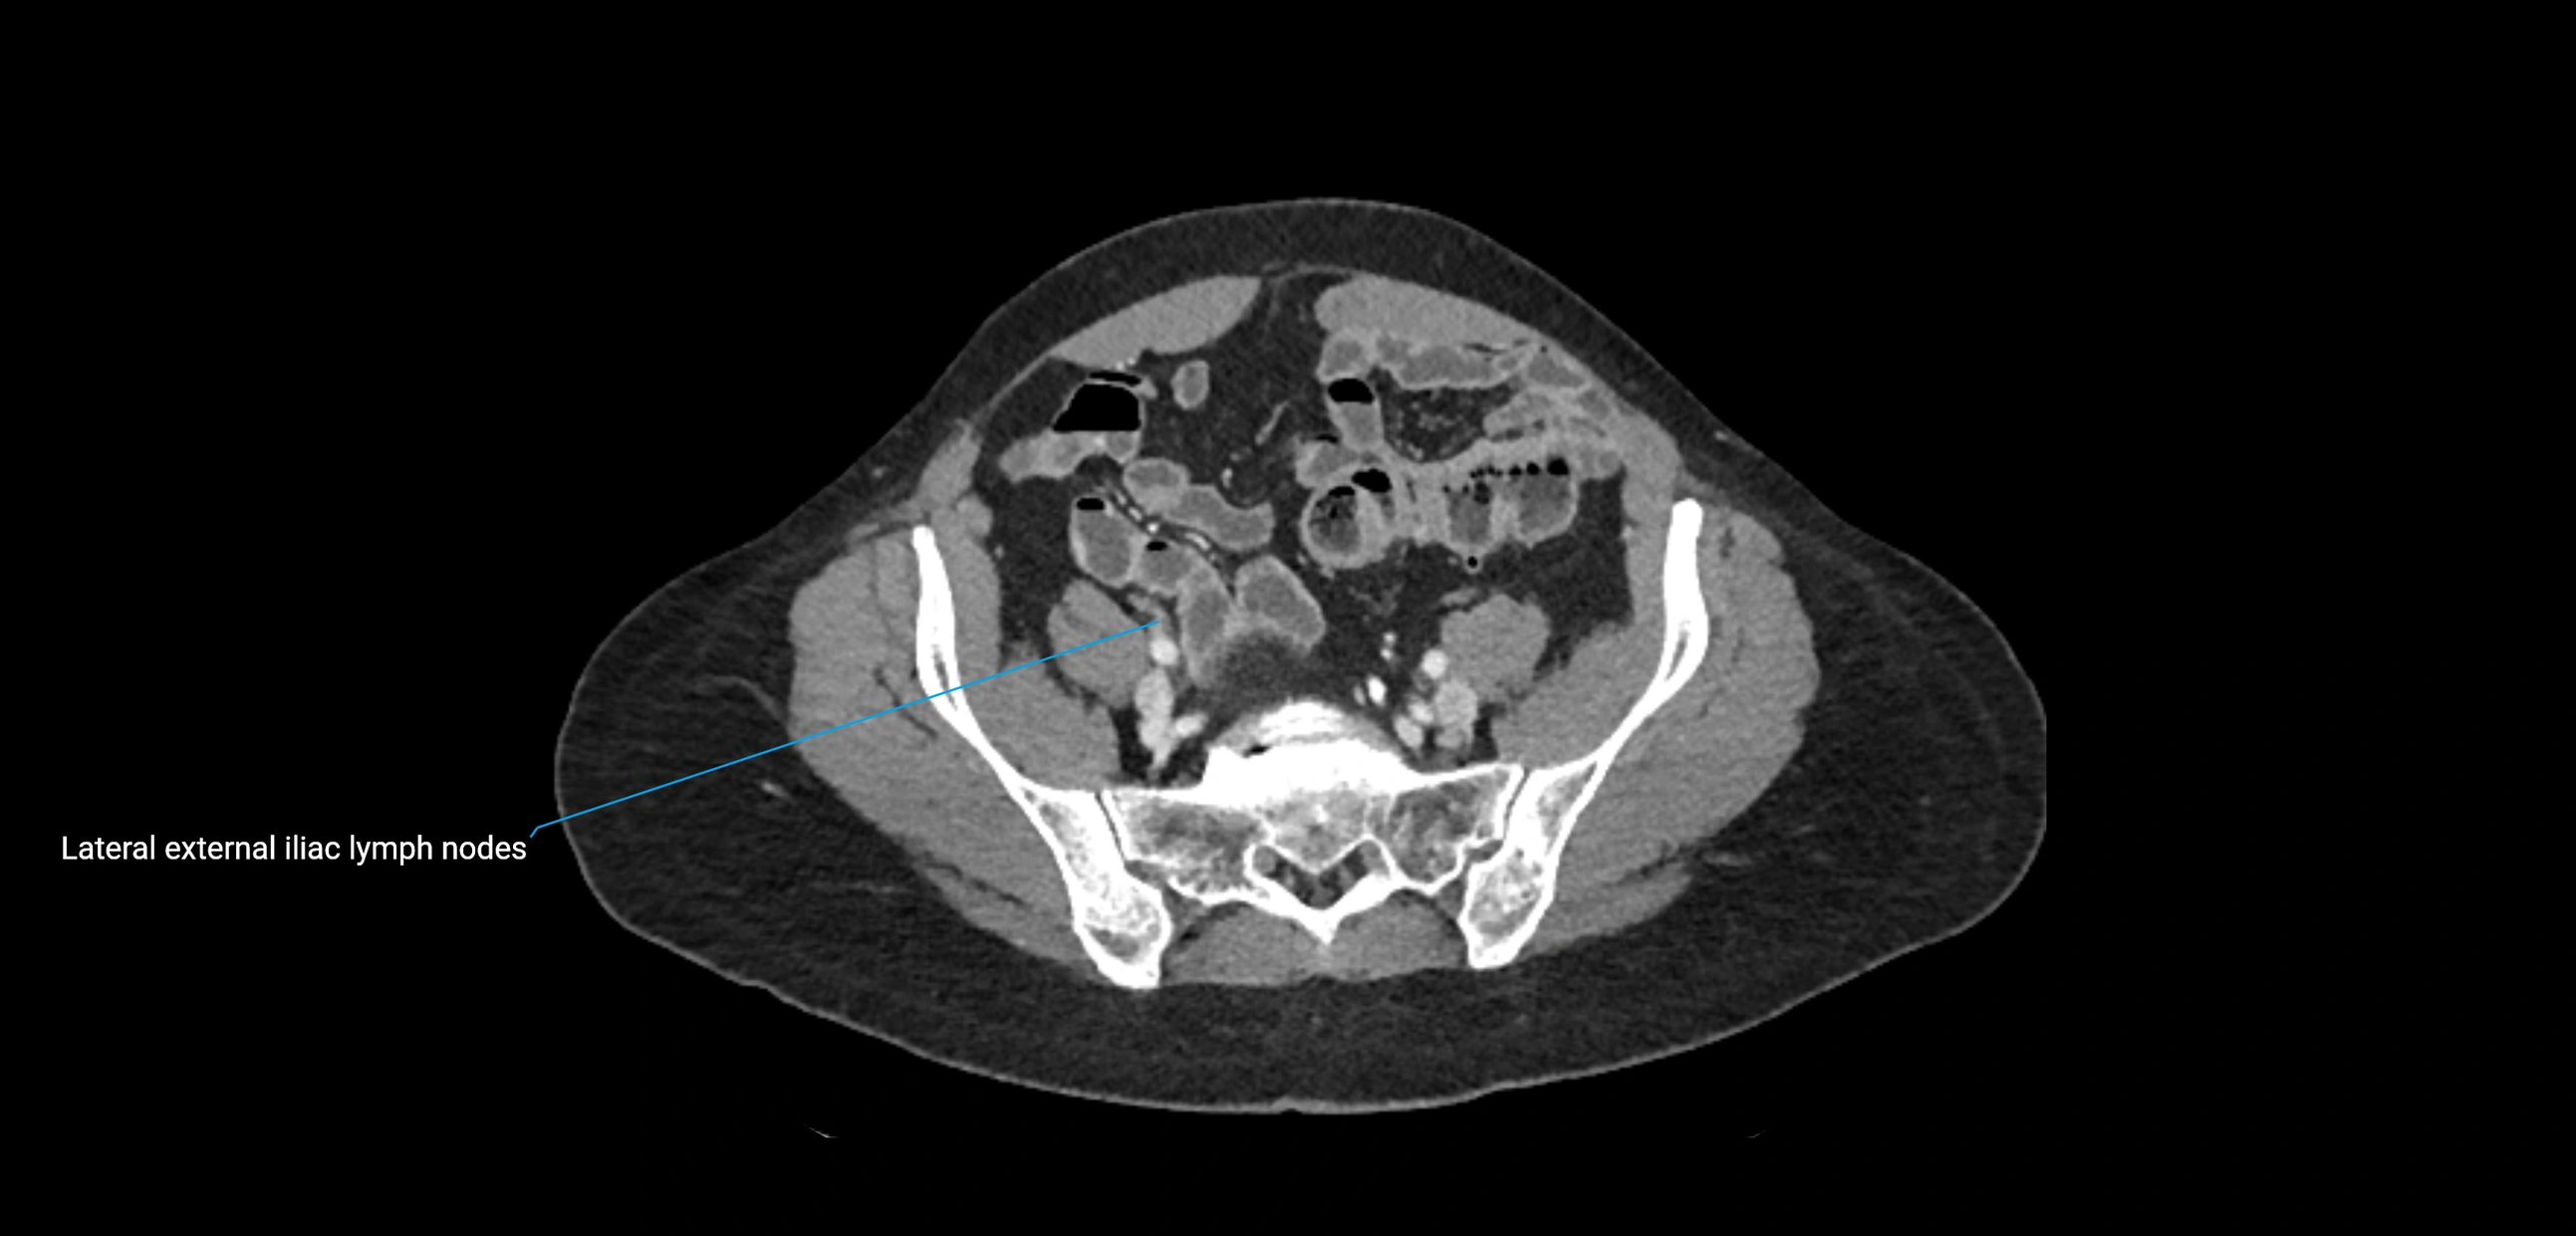

CT Appearance

CT Pre-Contrast:

• Nodes appear as soft-tissue density nodules adjacent to the aorta and IVC

• Calcification may be seen in chronic infections (e.g., tuberculosis)

CT Post-Contrast:

• Normal nodes enhance homogeneously

• Malignant nodes may show heterogeneous enhancement, central necrosis, or conglomerate formation

• Size >1 cm short axis is suspicious, though morphology and distribution are equally important

CT Venography (CTV):

• Demonstrates nodal encasement or compression of adjacent vessels (aorta, IVC, renal veins)

• Useful in staging testicular and ovarian malignancies

• Provides 3D reconstructions for retroperitoneal lymph node dissection planning